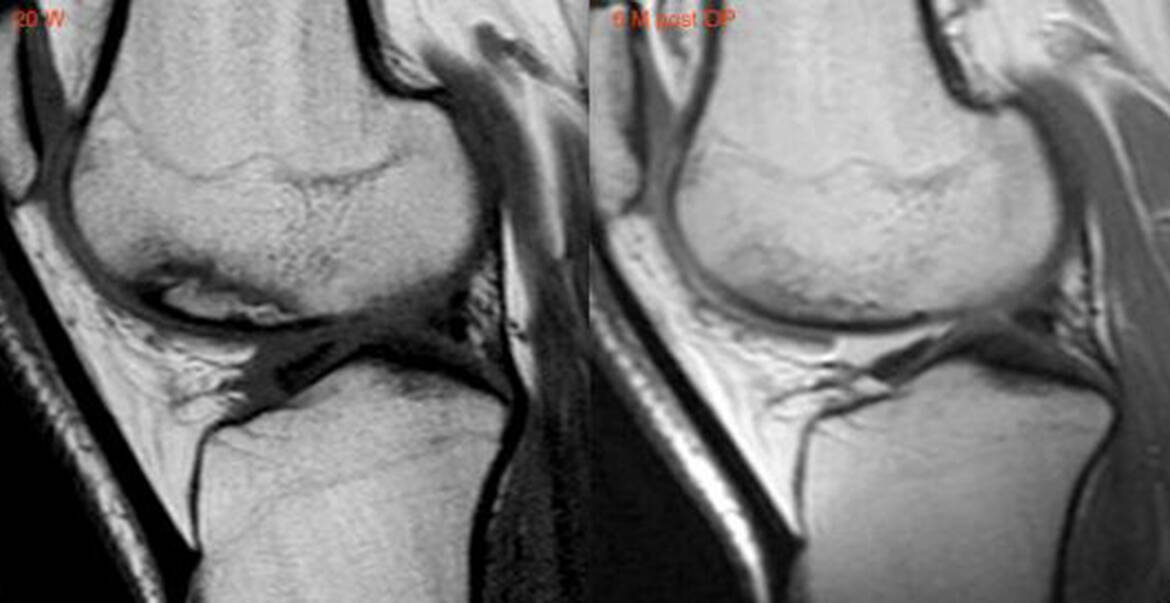

«К этой технологии меня привёл многолетний исследовательский и практический опыт работы в медицине. Вообще регенеративная медицина берет своё начало в европейских клиниках. Мой учитель – профессор Юрген Тофт, врач из Мюнхена, – является основоположником метода восстановления хряща коленного сустава. Это метод-предшественник моим технологиям. Полностью разрушенный хрящ коленного сустава при артрозе крайней – четвертой степени замещается новым хрящом. Прежде считалось, что восстановление хряща невозможно. Тофт наносил новые специальные повреждения в зоне пораженного участка, благодаря чему в течение приблизительно трёх месяцев вырастал новый хрящ», – рассказал врач.

Юрген Тофт является основоположником метода восстановления хряща коленного сустава. Он наносил новые специальные повреждения в зоне пораженного участка, благодаря чему в течение приблизительно трёх месяцев вырастал новый хрящ